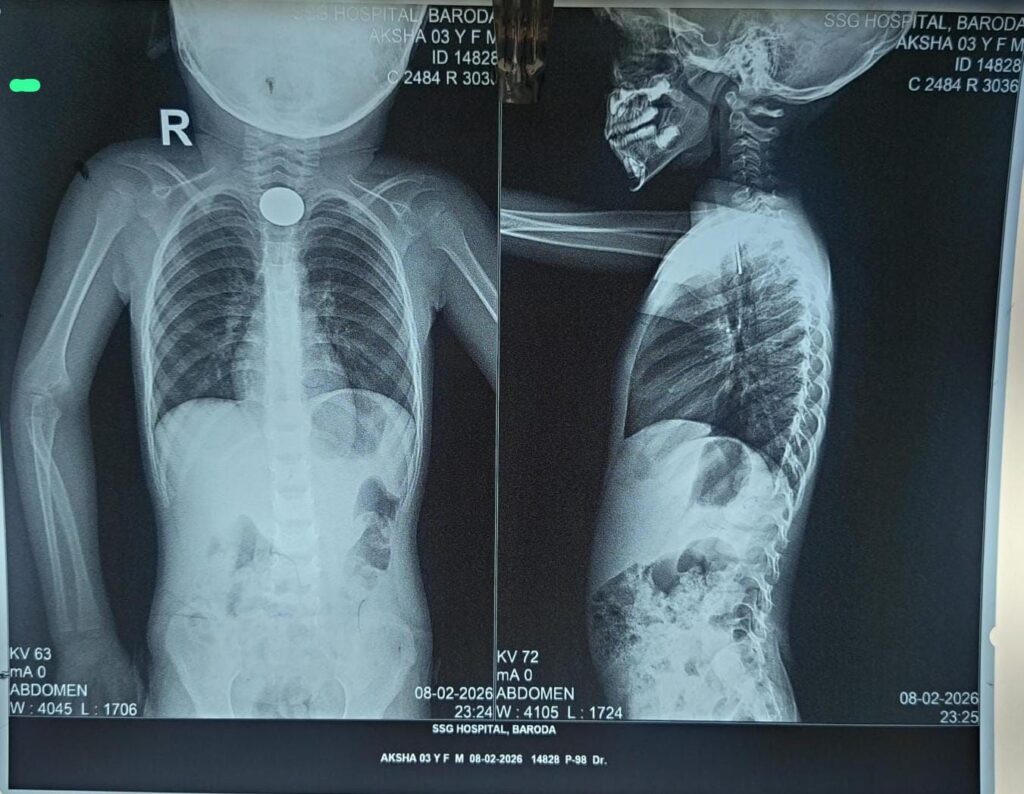

SSG હોસ્પિટલના ડોક્ટરો દેવદૂત બન્યા: 10 કલાકમાં બે બાળકોના જીવ બચાવતી જટિલ સર્જરી.